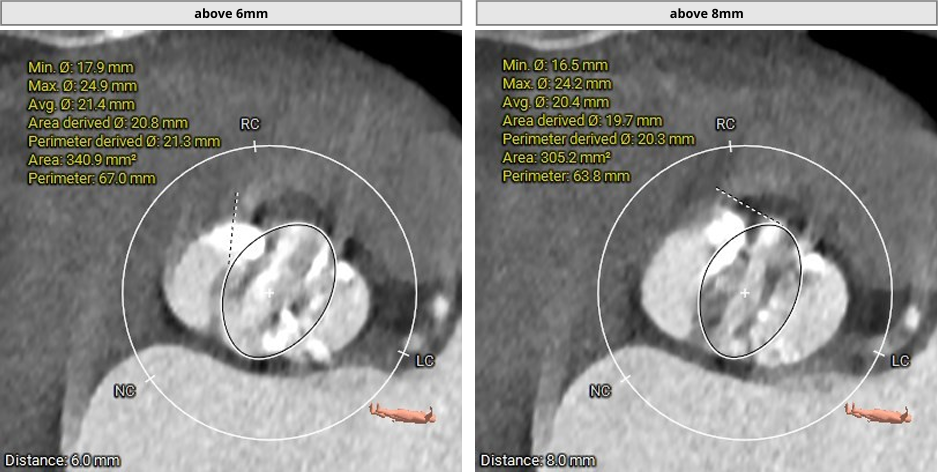

主动脉根部CT测量数据

瓣上结构评估

1. TYPE0型二叶瓣,根据主动脉根部CT评估情况,决定预选22mm球囊预扩,植入VenusAL26瓣膜。